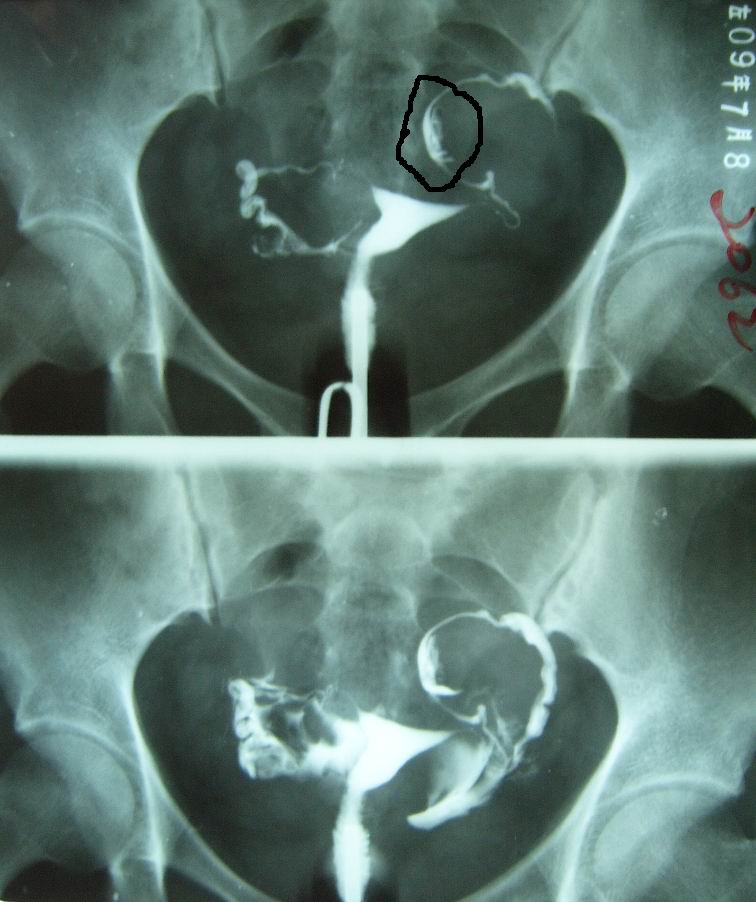

子宮子宮輸卵管造影(HSG)是一種經(jīng)子宮頸管和宮腔進(jìn)行插管和注藥的檢查方法,主要用于了解宮頸管、宮腔和輸卵管的通暢情況,是一種初步評(píng)子宮估輸卵管通暢度的檢查方法,也是不孕癥患者最基礎(chǔ)、最常規(guī)的檢查方法。檢查時(shí)需將導(dǎo)管插入宮腔,因而有因?qū)m頸瘢痕、粘連過緊導(dǎo)致檢查失敗的可能,也由于該項(xiàng)檢查的局限性,有因輸卵管痙攣造成輸卵管不通的假象的可能。